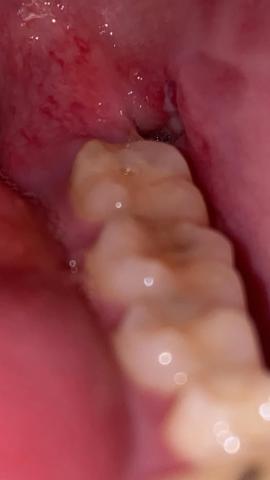

On Day 1, the socket appears dark red due to the blood clot.

By Day 2–4, the surface may turn white or cream-colored. This is a normal extraction wound look during the early healing stage.

The white appearance does not automatically mean pus.

Healing color progression:

• Dark red – blood clot

• White/cream – granulation tissue

• Pink – new gum forming